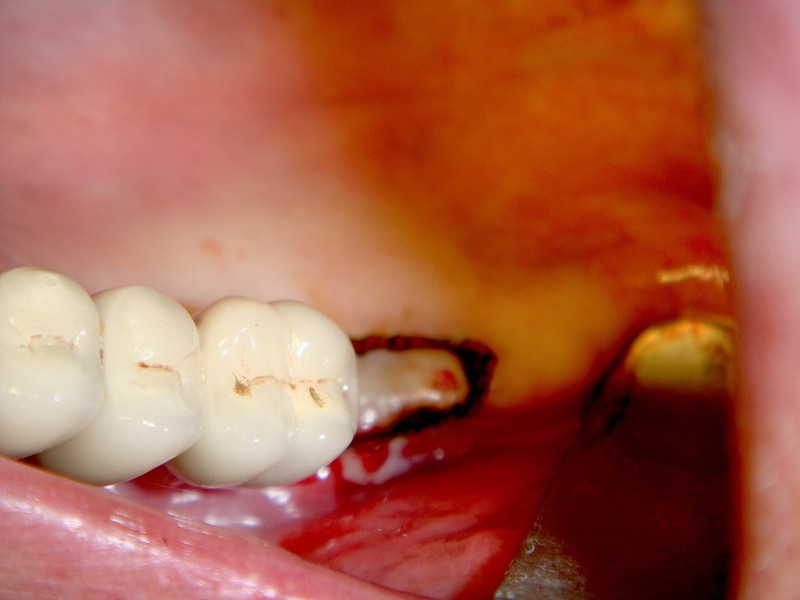

rigenerazione grave difetto parodontale a carico del 46